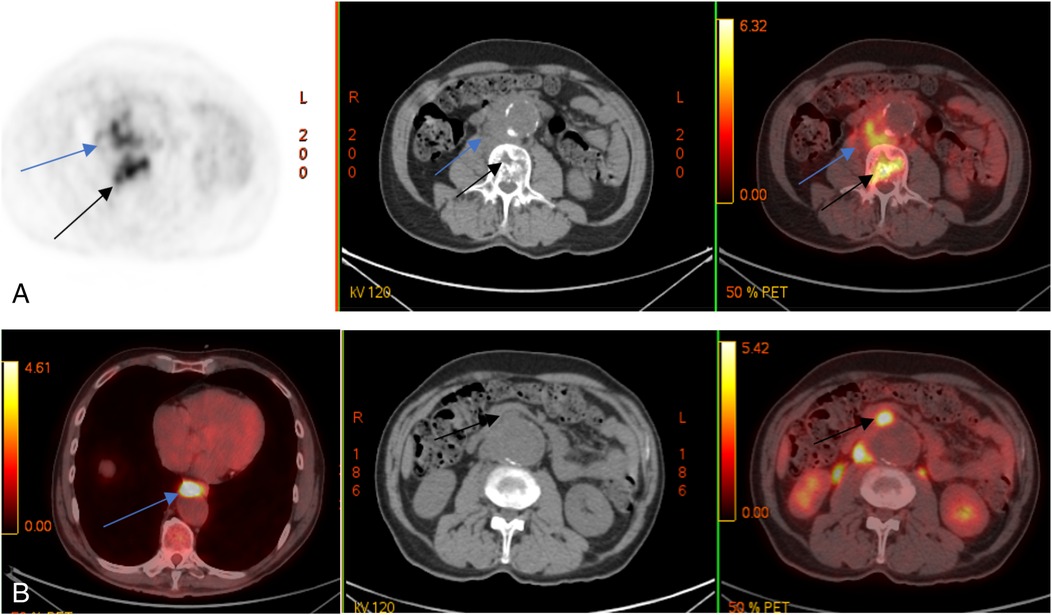

A follow-up MRI and PET/CT with 18F-FDG showed mixed results: a regression of inflammatory changes in the retroperitoneal infiltrate and L2–L3 vertebrae but new lesions in the L4 vertebral body (Figure 3).

Figure 3

Control PET/CT with 18F-FDG. Multidirectional dynamics: decrease of metabolic activity in lumbar vertebral bodies (black arrows) and m. psoas on the right side (blue arrows) (A); appearance of metabolically active changes anterior to the descending thoracic (blue arrow) and abdominal aorta (black arrows) (B).

Antimicrobial therapy was subsequently adjusted to vancomycin 20 mg/kg administered intravenously every 12 h and moxifloxacin 400 mg delivered intravenously once daily. Despite this, PET/CT revealed additional lesions involving the Th10 vertebral body, intrathoracic, axillary, and retroperitoneal lymph nodes, spleen, and basal segments (S1–S2) of the left lung.